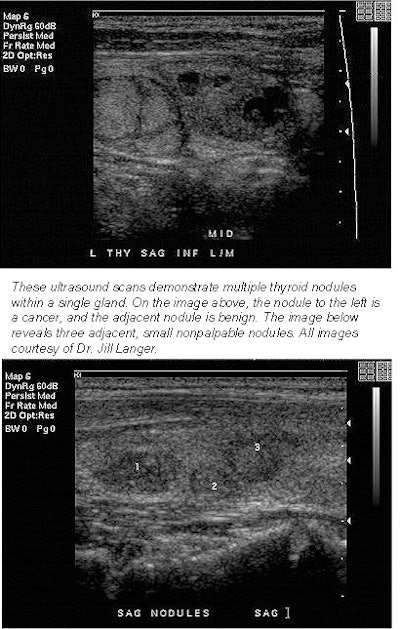

The study, led by associate professor of radiology Dr. Jill Langer, could help answer a lingering question in thyroid ultrasonography: What to do with the growing number of small nodules detected only on ultrasound? Currently, the only research-based patient management algorithm concerns palpable nodules. Conventional wisdom holds that because solitary palpable nodules are more likely to be cancerous than multiple nodules, most solitary palpable nodules should be biopsied.

They retrospectively reviewed the records of 399 patients who had undergone ultrasound-guided biopsy for two types of nodules: those larger than 1 cm as seen on ultrasound, or if three or more large nodules were detected, those that looked suspicious on the 123-iodine scan. The cancer risk was virtually the same in both groups: 16% in patients with solitary nodules and 15% in patients with multiple sub-centimeter or red-flagged nodules as per the iodine scan.